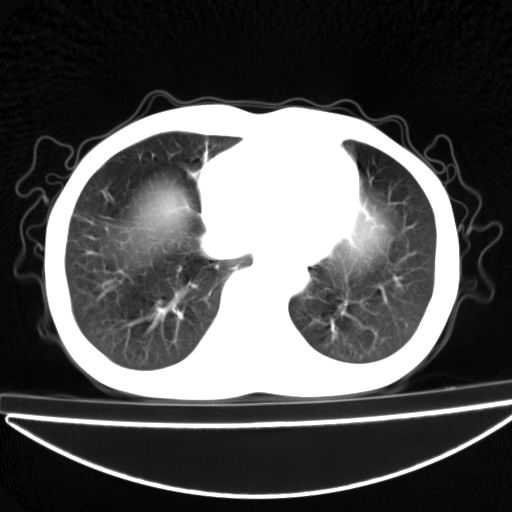

以下是引用杀毒软件在2009-4-28 17:58:00的发言:[br]考虑----左肺慢性肺脓肿形成继发上叶含气不良---抗炎后复查---待排肿瘤所致[br][br][本贴已被 杀毒软件 于 2009-4-28 18:01:26 修改过]